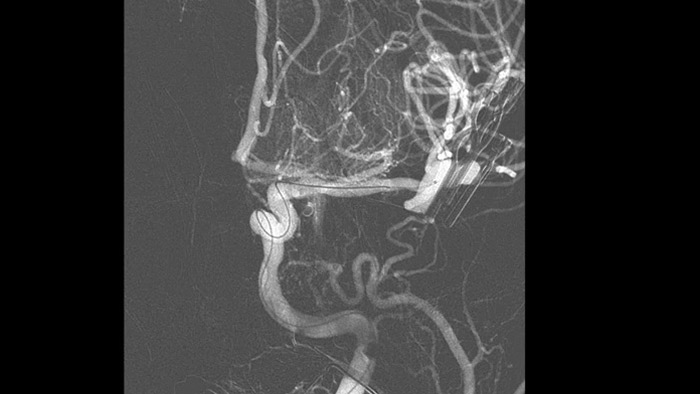

SmartCT Angio is an X-ray acquisition technique that generates a complete high-resolution 3D visualization of cerebral vasculature from a single rotational angiography run – all controlled via the touch screen at the table. This can improve visibility of tortuous or complex anatomy.

SmartCT Vaso provides high resolution 3D imaging that reveals key information about cerebral vascular structures to support the highest possible spatial assessment of vessels in the soft tissue context.

SmartCT Angio provides a volumetric view in a few seconds1 to assist assessment of location, size, neck, and severity of aneurysm for treatment planning. 3D volumes are visualized with high spatial resolution and automatic patient movement compensation.